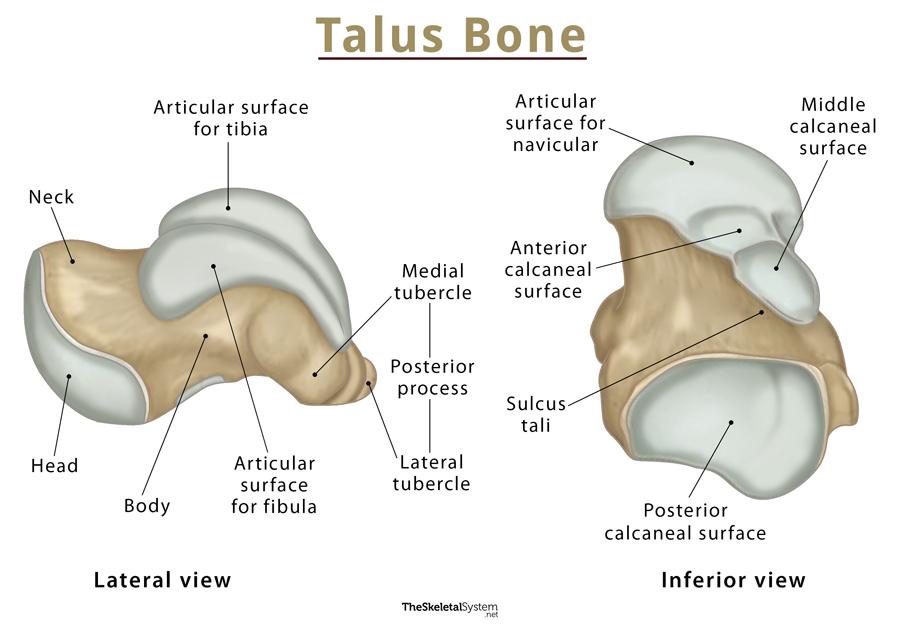

does the talus have any muscular attachments?

no muscular attachments, but has ligaments

what is the talus composed of?

head

neck

body